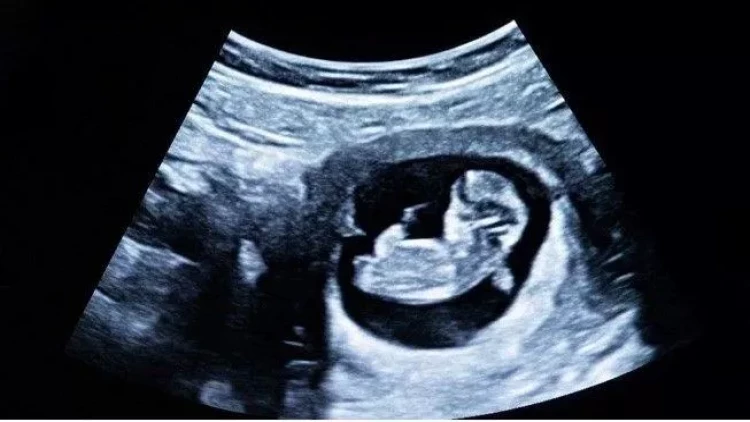

Alimlər hamiləlik dövründə ana bətnində inkişaf edən döllərin amnion mayesindən (dölyanı su) götürülən hüceyrələrdən "mini orqan"lar istehsal etməyə nail olublar.

meqale.com medicina.az-a istinadən xəbər verir ki, ana bətnində olan dölün qidalanması və qorunmasını təmin edən amnion mayedən alınan ağciyər, böyrək və bağırsaq hüceyrələrindən "orqanoid" adlanan 3D toxuma qranulları yaradılıb.

Bu "orqanoid"lər insanın inkişafı və xəstəliklərin dərk edilməsində böyük əhəmiyyət kəsb edə bilər. Araşdırmalar göstərir ki, yetişdirilən bu kompleks hüceyrə modelləri körpənin bioloji məlumatlarını qoruyur.

Bildirilir ki, "mini orqanlar" körpənin inkişafı zamanı baş verən anormal formasiyaların səbəbləri və inkişafının qarşısını almaq üçün çox vacib olacaq.

Bu, dölün inkişafının daha yaxşı başa düşülməsinə və vaxtından əvvəl doğuş riski kimi problemlərin həllinə gətirib çıxaracaq. Bundan əlavə, bu texnologiyanın xəstəliklərin müalicəsində yeni yanaşmaların işlənib hazırlanmasına imkan verəcəyi düşünülür. Məsələn, körpədə anadangəlmə bir xəstəliyin aşkarlanmasına və doğuşdan əvvəl müalicəsinə kömək edə bilər.

Araşdırma ana bətnində olan döllərin inkişafını daha dərindən anlamaq və vaxtından əvvəl doğuş kimi fəsadların qarşısını almaq üçün perspektivli addım hesab olunur. Ümid edilir ki, orqanoid texnologiyası inkişaf etdikcə daha çox xəstəliklərin müalicəsində əhəmiyyətli irəliləyişlər əldə ediləcək.